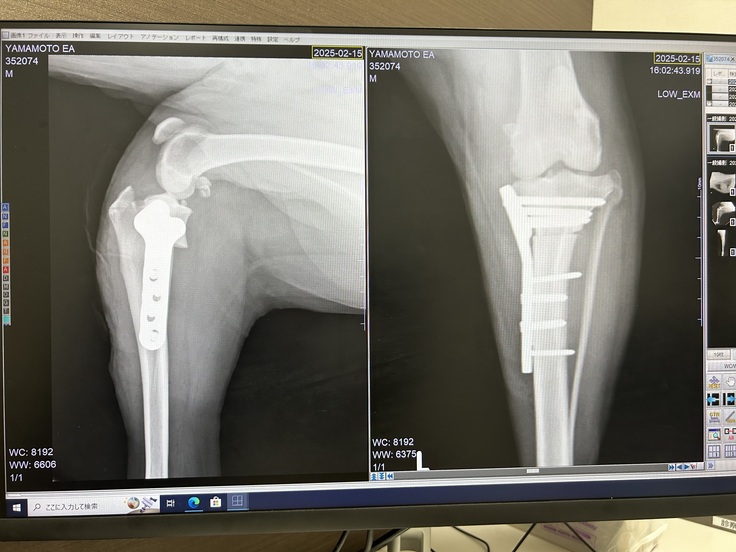

術後経過(1w/レントゲン)

レントゲンで確認しました。

経過はよいみたいで、切れた靭帯は治らないのですね。

TPLOと言うのは、骨を切ってこんなことになるのか。ショックです。すまんことをした。

😨抜糸は来月。治りますように。